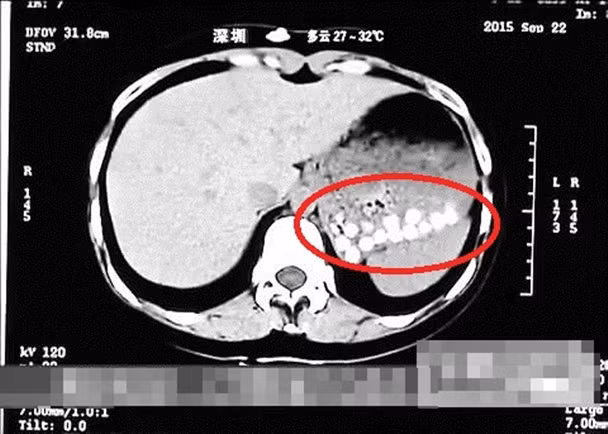

Cụ thể, theo thông tin được đăng trên tờ Hong Kong Free Press, trong chương trình thực tế Life Help, phóng viên ở Thanh Đảo (Sơn Đông, Trung Quốc) đã tới uống trà sữa trân châu trong một cửa hàng địa phương rồi tới bệnh viện chụp CT. Kết quả CT scan cho thấy, trong dạ dày của phóng viên này có những viên trà sữa trân châu không thể tiêu hóa được.

| Kết quả chụp CT cho thấy các hạt trân châu dồn về 1 phía trong dạ dày, không thể tiêu hóa. |